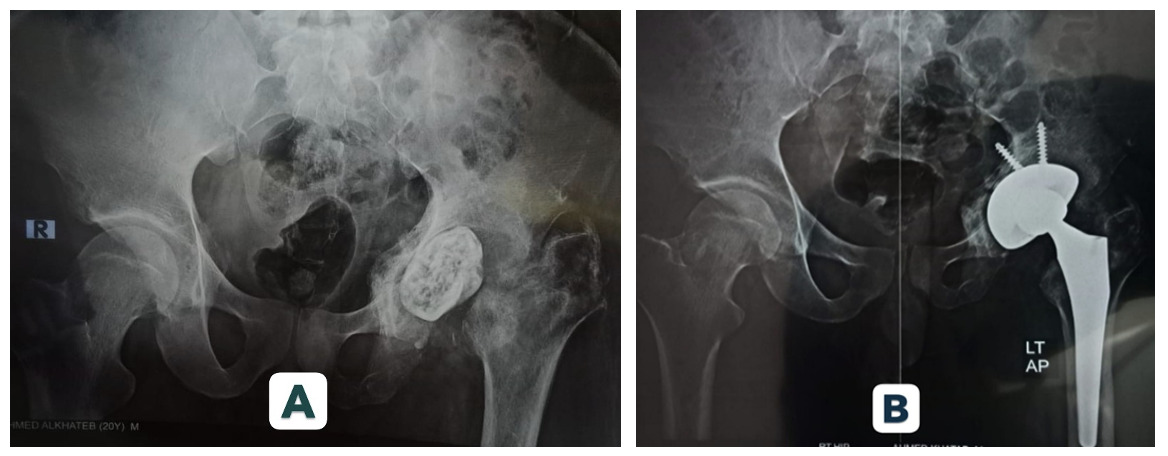

At final follow-up, 95.5% of Mega Cup reconstructions remained in situ, with no evidence of loosening. Kaplan–Meier analysis demonstrated a 95% cumulative survival rate at 5 years. Radiographic assessment confirmed stable fixation in 90.9% of hips. Graft incorporation was observed in 88.9% of cases. (Figures 1 and 2 illustrate radiographic outcomes.)

Kaplan–Meier analysis revealed a 95% 5-year survivorship rate, consistent with mid-term outcomes reported by Wang3 (>90%) and aligning with the favorable long-term results documented by Oommen4 at 10–14 years. Radiographic stability was achieved in 90.9% of hips, and graft incorporation was observed in 88.9% of cases. These findings parallel outcomes reported for porous titanium and tantalum constructs, reinforcing the biological advantage of highly porous shells in promoting osseointegration.5–8